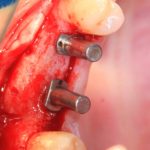

Далее, можем приступить к установке имплантатов. Разумеется. по хирургическому шаблону:

Последняя картинка даёт представление о том, какой объем костной ткани мы «нарастили».

Поскольку принимающее ложе и аутокостный блок конгруэнтны, мы можем отказаться от использования барьерной мембраны. Она не нужна.